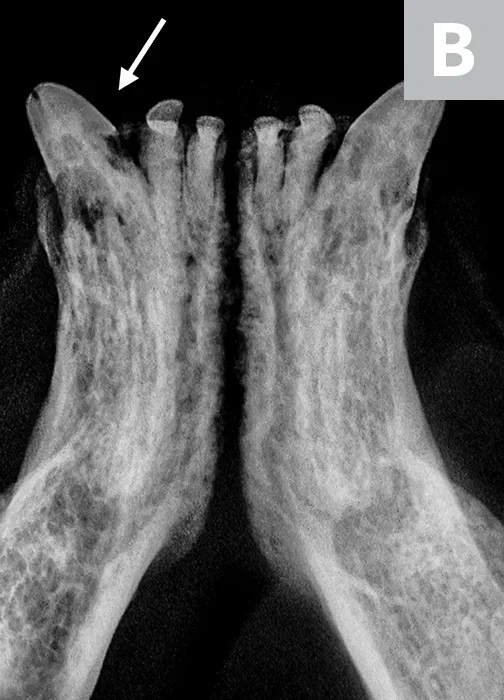

Tooth resorption type is determined via intraoral radiography based on root opacity and periodontal ligament space (see Types of Tooth Resorption Based on Radiographic Appearance and Figure 2).

Radiograph of a left mandibular molar tooth in a cat with Type 1 resorption (A) in which focal or multifocal radiolucency can be seen with otherwise normal radiopacity and normal periodontal ligament space. Radiograph of mandibular incisors and canine teeth in a cat with Type 2 resorption (B; white arrow) in which narrowing or disappearance of periodontal ligament space is present in at least some areas, and part of the tooth demonstrates decreased radiopacity. Radiograph of the right maxillary third and fourth premolars in a cat with Type 3 resorption (C); the third premolar features Type 1 resorption of the mesial root (arrowhead) and Type 2 resorption of the distal root (dashed arrow) with exposure to the oral cavity.

Type 1 (T1): focal or multifocal radiolucency in a tooth with otherwise normal radiopacity and normal periodontal ligament space

Type 2 (T2): decreased radiopacity in part of a tooth with narrowed or absent periodontal ligament space in at least some areas

Type 3 (T3): features of Type 1 and Type 2 in the same tooth; focal or multifocal radiolucency in a tooth and decreased radiopacity in other areas of the tooth with areas of normal and narrow or lost periodontal ligament space